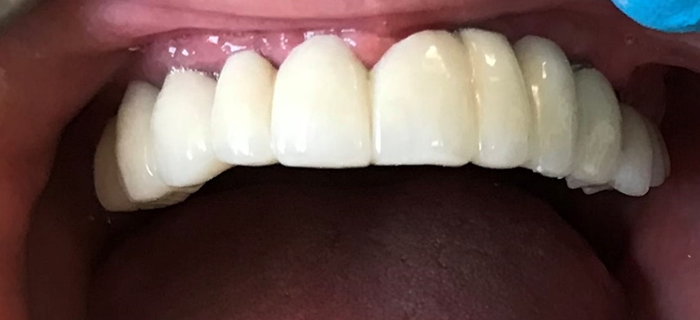

Resident Case Photos

The following are before and after photos of dental patients who have been treated by the residents at NYC Health + Hospitals/South Brooklyn Health. To apply to the program visit the Dental GPR Page and click on Application Information.

Crowns